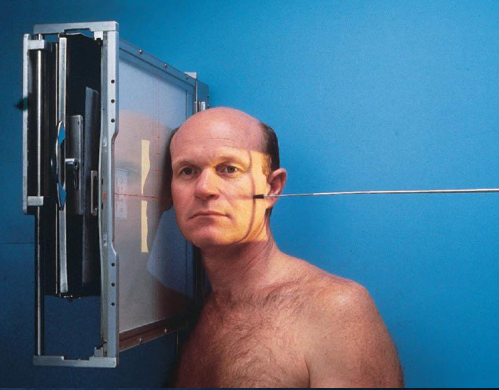

Lateral skull

patient position:

upright or semiprone

part position:

MSP of head parallel to IR

IPL perpendicular

IOML perpendicular to front edge of IR

respiration suspended

CR:

perpendicular to IR

enters 2 inches above EAM

collimation:

1 inch beyond skin line of the skull